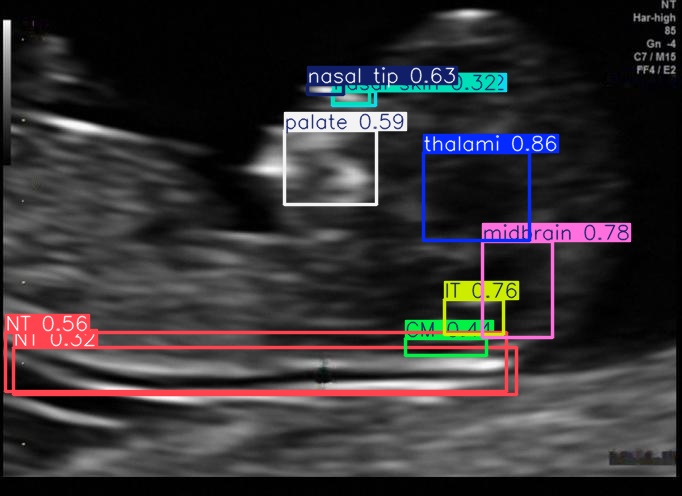

Testing on a sample test image